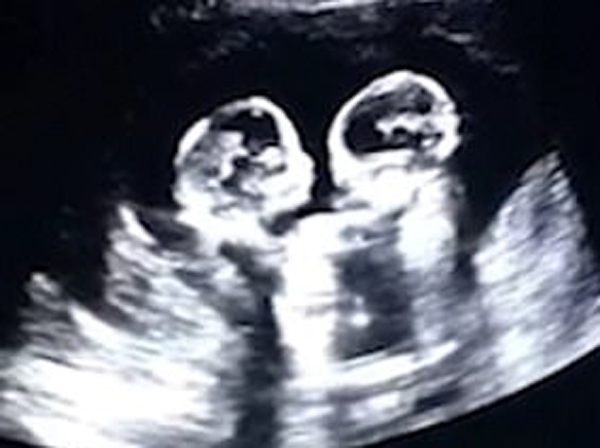

చైనాలోని యించువాన్ నగరంలో ఇలాంటిదే ఓ అరుదైన సంఘటన జరిగింది. కొన్నాళ్ల కిందట.. ఇద్దరు భార్యాభర్తలు రెగ్యులర్ ప్రెగ్నెన్సీ అల్ట్రా సౌండ్ స్కానింగ్ కోసం హాస్పిటల్ కు వెళ్లారు. అక్కడ స్కానింగ్ కవలలు ఉన్నారని తెలిసి సంబరపడ్డారు. అలాగే.. ఓ సందర్భంలో… వారి ఎదుగుదలను , కదలికలను గమనిస్తున్నప్పుడు.. వారిద్దరూ ఒకరిపైకి మరొకరు రావడంతో… ఒకరినొకరు చేతులతో కొట్టుకోవడం.. ఒకరినొకరు హగ్గింగ్ చేసుకోవడం కనిపించింది. ఇది చూసిన భర్త తావో.. దానిని వీడియో తీశాడు. కడుపులో ట్విన్స్ చేసిన అల్లరికి ఆ తల్లిదండ్రులు ముచ్చటపడ్డారు. ఆ వీడియో ఇపుడు సోషల్ మీడియాలో వైరల్ అయిపోయి ప్రపంచమంతా తిరుగుతోంది. అమ్మ కడుపులో ఉన్నప్పుడే కవలలు చేసిన అల్లరిని చూసి.. ఇపుడు ప్రపంచమంతా ముచ్చటపడిపోతోంది.

ఆ తల్లిదండ్రులు కొద్దిరోజుల కిందట ఇద్దరు ఆడపిల్లలకు జన్మనిచ్చారు. వారిద్దరికీ గమ్మత్తైన పేరు పెట్టుకున్నారు. ఒకరి పేరు చెర్రీ .. మరొకరి పేరు స్ట్రాబెరీ. సూపరున్నాయిగా ఆ కొంటె పిల్లల పేర్లు. వాళ్లు ఈ భూమిమీదకు రాకముందే జనాలకు బాగా తెలిసిపోతారని తాను ఊహించలేదని ఆ తల్లిదండ్రులు ఆనందంతో చైనీస్ మీడియాకు ఇచ్చిన ఇంటర్వ్యూల్లో చెప్పారు. మీరూ ఓసారి ఆ వీడియో చూసేయండి.